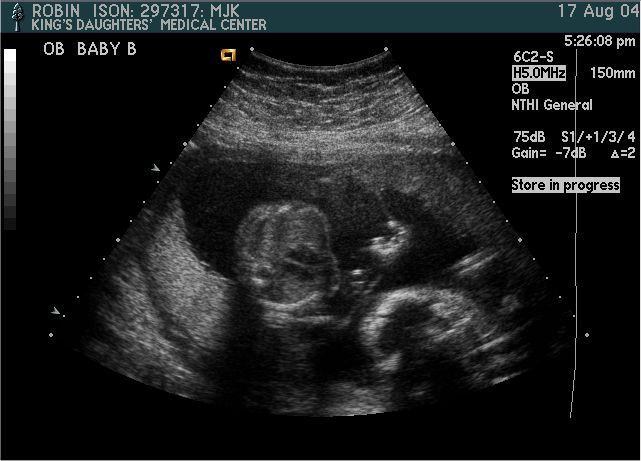

Baby B

Pictures from Ultrasound at 20 weeks.